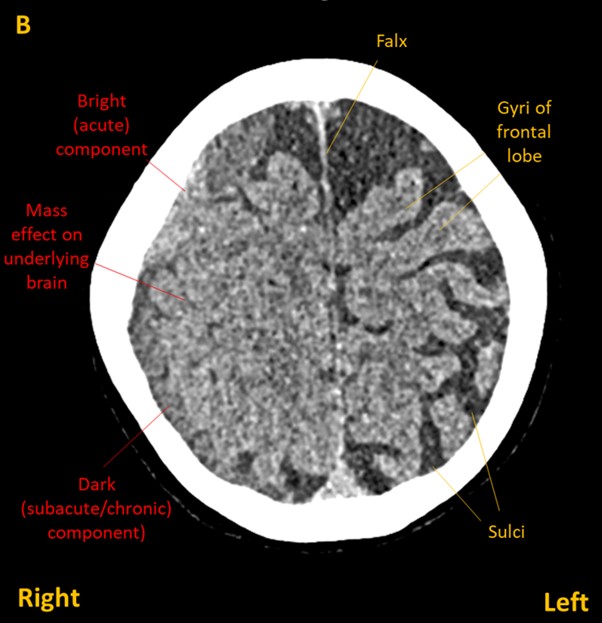

A CT brain showed and right frontoparietal subdural haematoma (images A&B) with a small amount of midline shift (C).